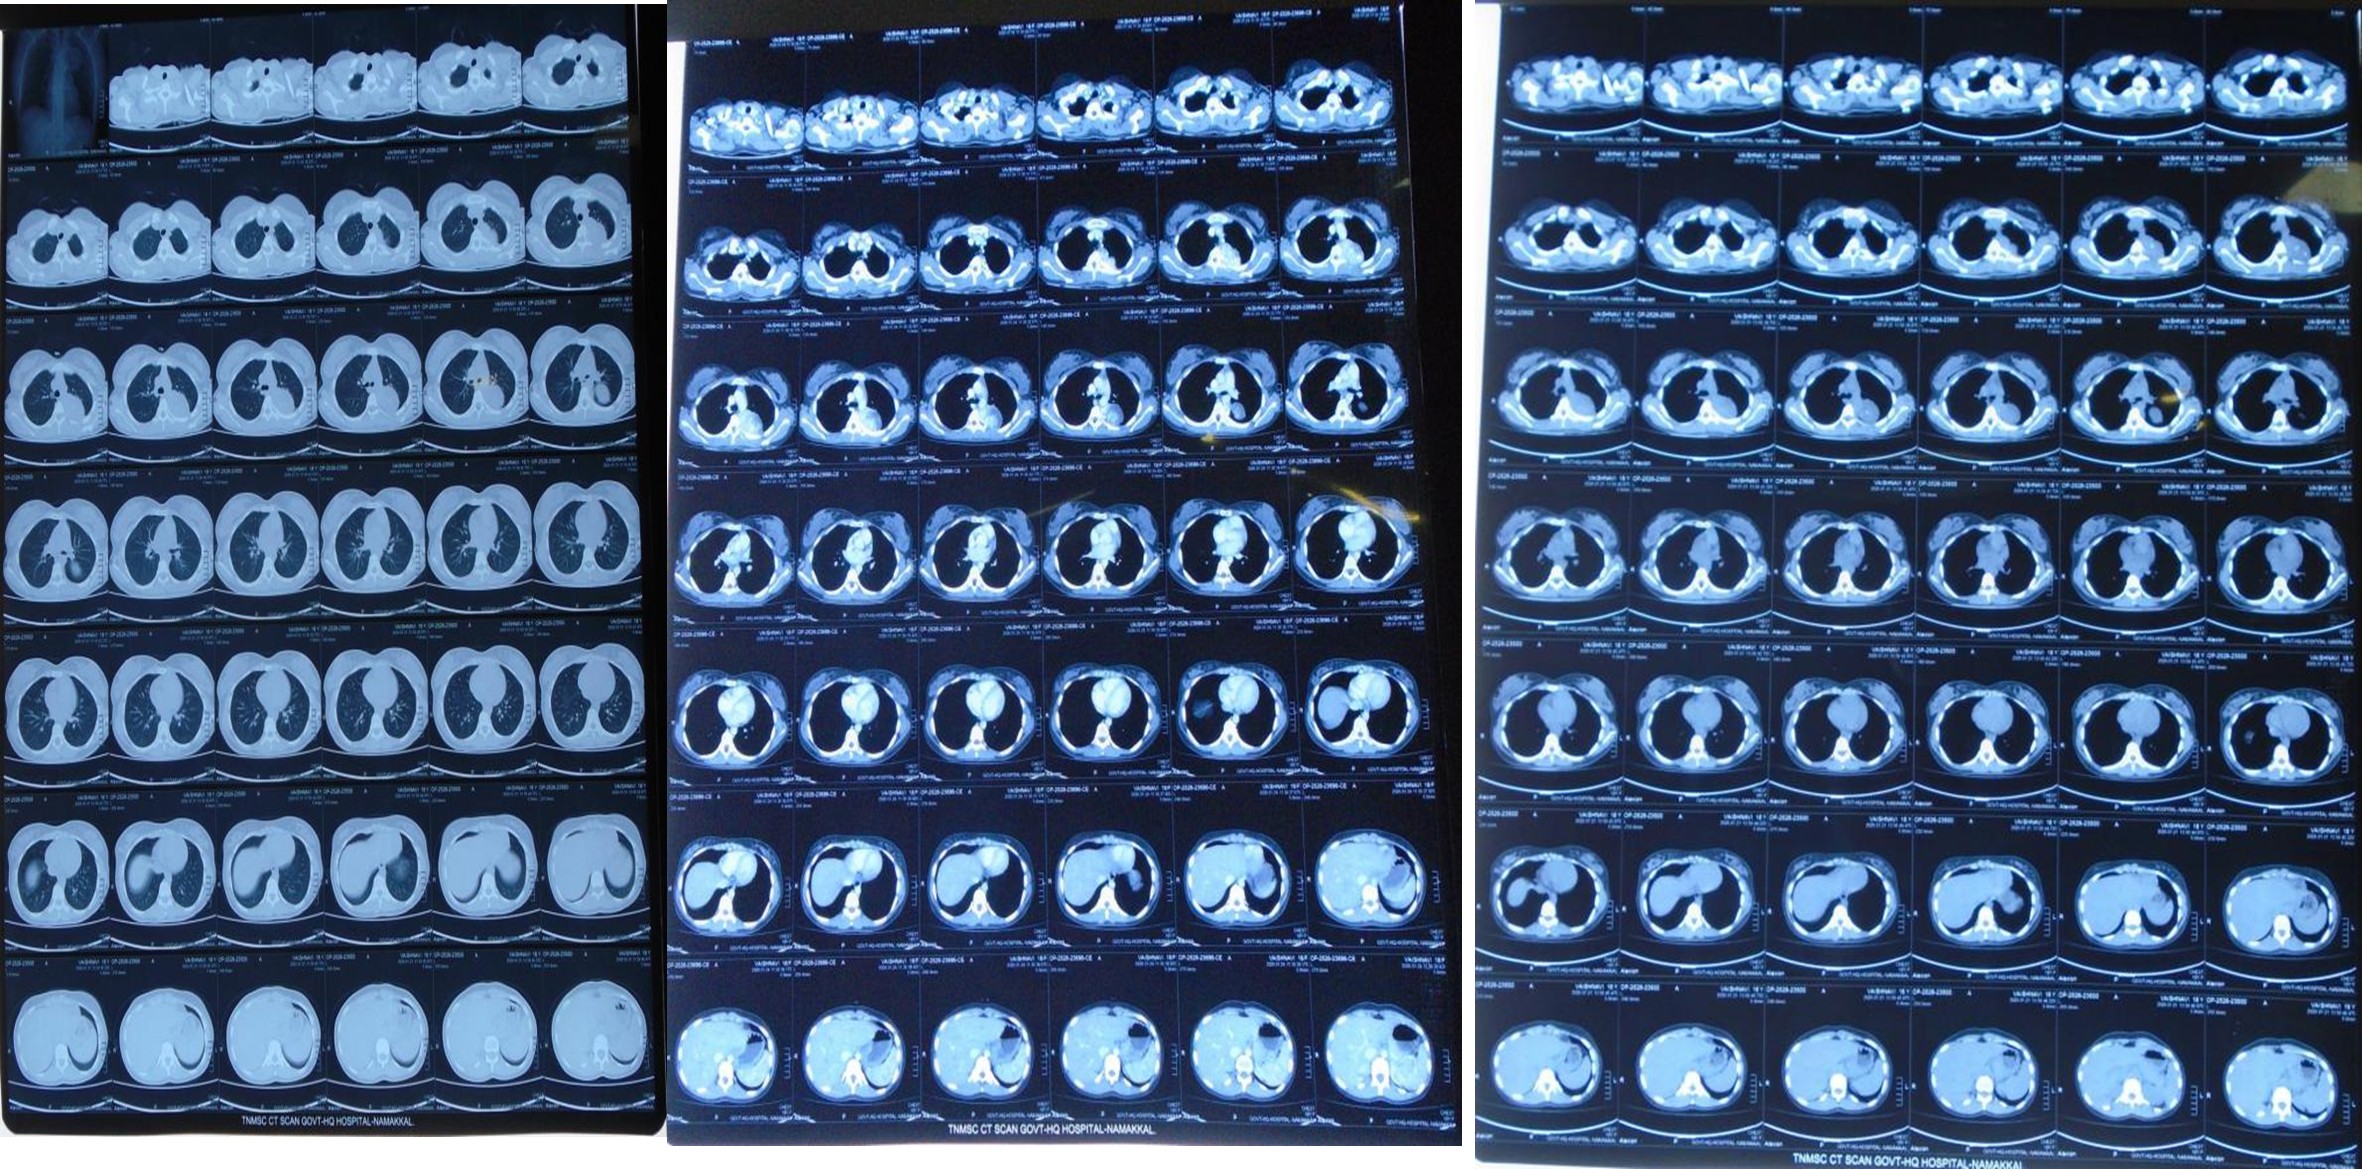

CT scan – Thorax Plain

Impression

- Osteochondroma away from left 4th

- Pulmonary Hematoma.

- Malignant peripheral nerve sheath tumor.